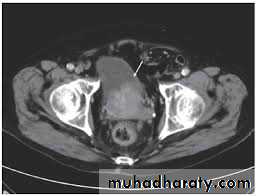

MRI and CT Scan